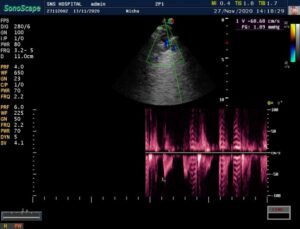

CARDIAC screening of the baby was done – is fourth week of life. Showed –

> Acyanotic congenital heart disease.

VSD – 5mm – muscular non –

restrictive.

ASD – 4mm – L-R shunt

PDA – 2.5mm – L-R shunt. Baby under follow up.